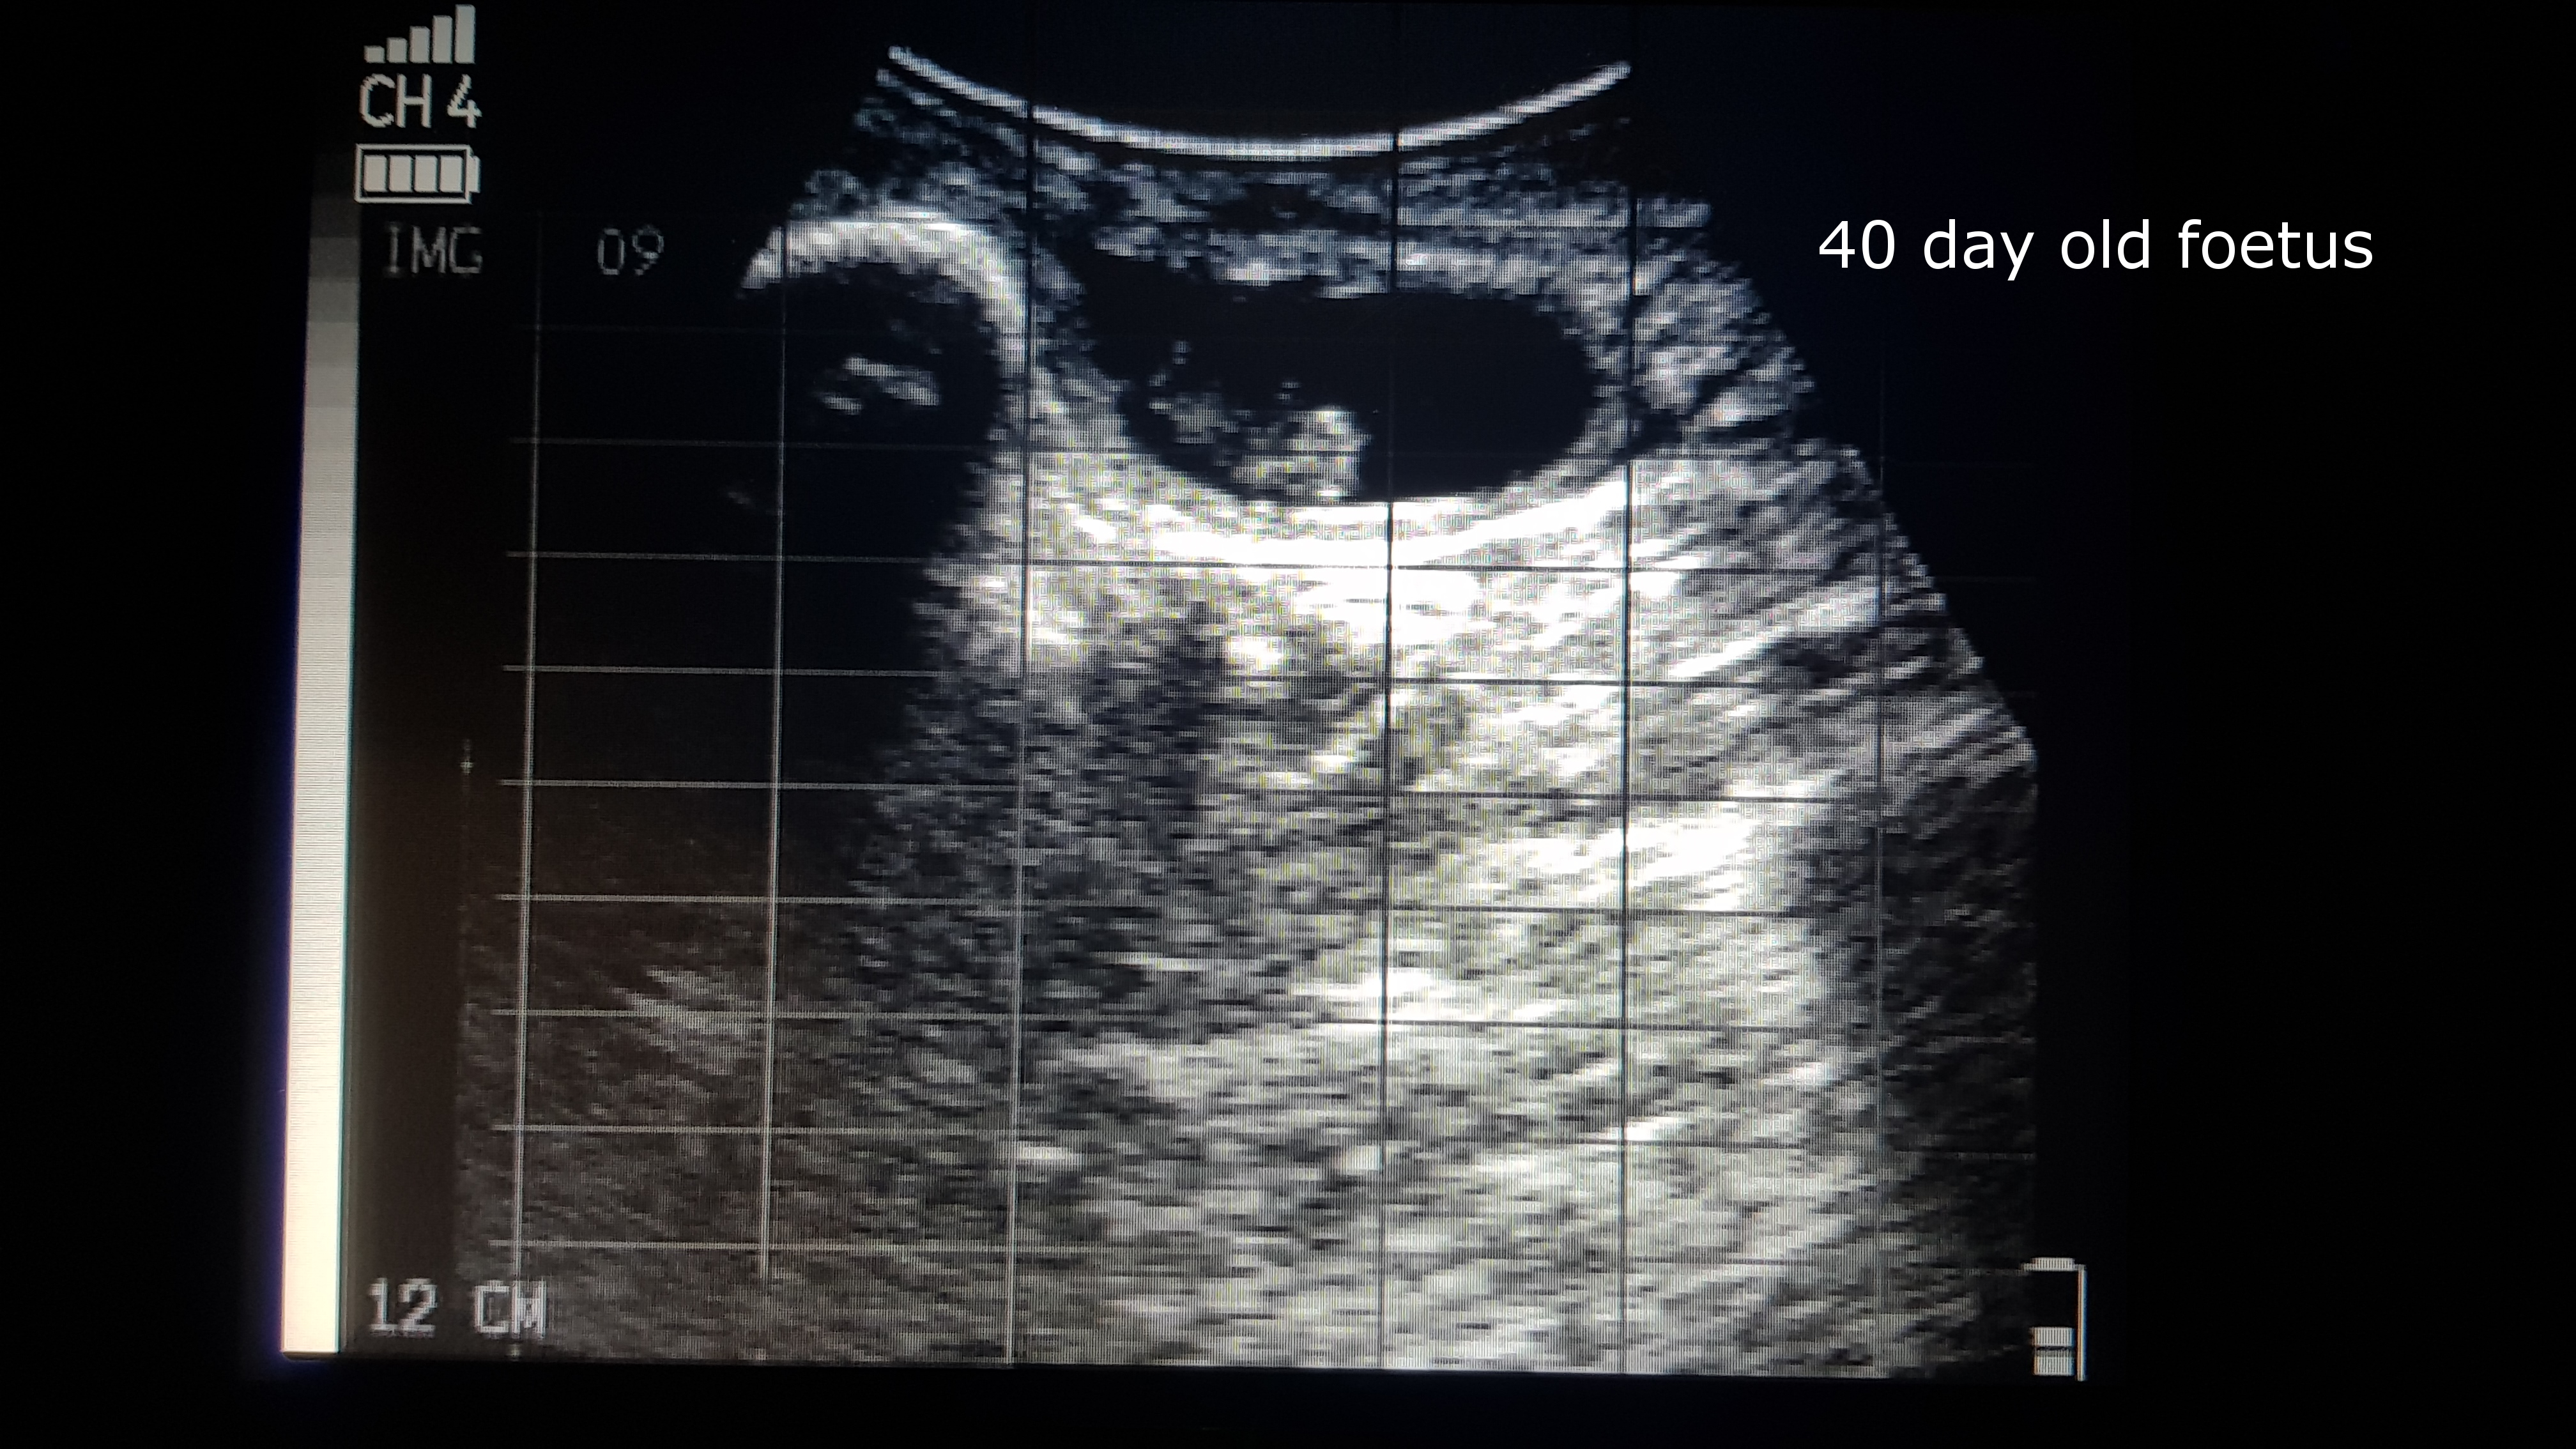

This more advanced service not only determines whether each individual cow is in calf or not, but also provides an estimate of how old the calf is. Foetal aging is most accurately carried out between 40 and 100 days of gestation. Once the pregnancies advance, there is too much variation in foetal size to be accurate and often the foetus is sitting too low to be measured correctly. Therefore, it is important to plan ahead and scan early. Foetal aging in beef cattle has many advantages, including:

Click to enlarge images. These are examples of how first trimester pregnancies can be aged, either by measuring the head width or body length of the foetus.